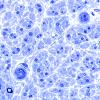

VASCULAR

Hypoxia-Ischemia, fetal-neonatal

White Matter (11)